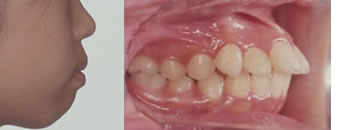

■2期治療開始時(11歳9ヶ月)

乳歯から永久歯に生えかわりました。歯ならび咬み合わせは少し出っ歯が戻っていますが、大きく乱れてはいません。しかしながら口元は大きく突出し已然として口唇閉鎖は困難な状況です。そこで当初の予定通り上下顎の第一小臼歯〔4番目の歯4本〕を抜歯して永久歯の治療をスタートしました。